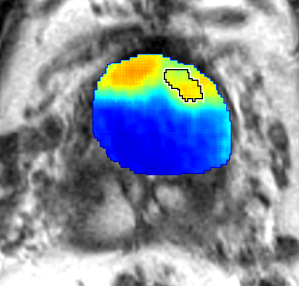

Training: From the 66 patients in the training cohort, we sampled all the cancer pixels from within the prostate, and randomly sampled an equal number of non-cancer pixels, also from within the prostate, thereby generating a training set of pixels, with equal number of cancer and non-cancer pixels. This ensured that we train the CorrNet with a balanced dataset of two classes. We used to weigh the cross-correlation error higher than the reconstruction errors. We chose a squared error loss for the reconstruction errors. We trained the CorrNet model with varying hidden layer dimensions, namely: . For each , we used a learning rate , and 300 training epochs. Figure 2 shows CorrNet representations of an example MRI slice, with .

Qualitative Evaluation: Figure 4 shows the same slice as in Figure 2 with aligned T2W, ADC, and histopathology images, and prediction results using current state-of-the-art method [4], our CorrSigNet() and CorrSigNet(T2W, ADC, ) models. It may be noted that [4] fails to detect the cancerous regions on the left and right of the images, while the CorrNet representations alone can identify the cancer regions, and when combined with T2W and ADC images, they predict the cancer regions with high probability. It may also be noted that CorrSigNet(T2W, ADC, ) shows fewer false positives than [4]. This example shows the strength of learning correlated MRI signatures in identifying subtle, and sometimes MRI-invisible cancers. Figure 5 shows more example slices from different patients, comparing the state-of-the-art approach [4] and our prediction results with CorrSigNet(T2W, ADC, ). We note that our model with correlated features (1) can identify subtle and smaller cancer regions, (2) have better overlap with ground truth cancer labels, and (3) have fewer false positives.